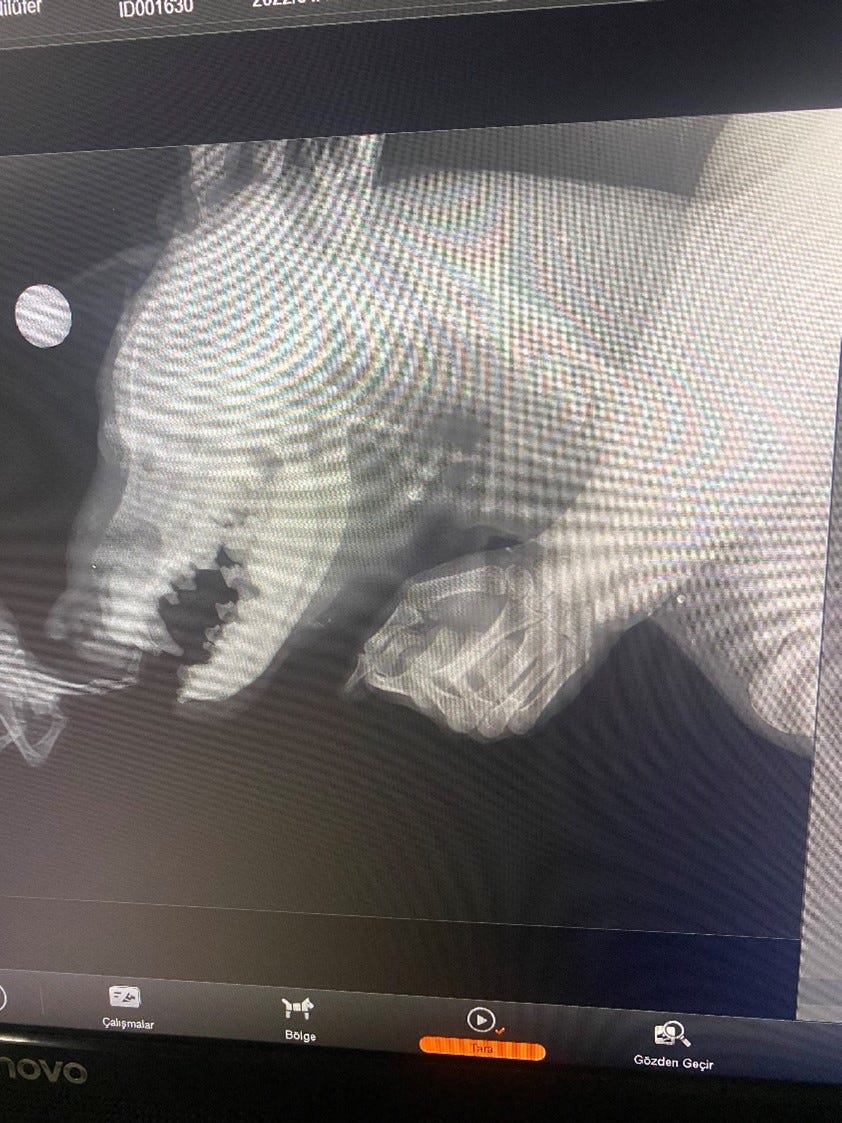

When x-rayed, Pamuk was found to have a number of bullets lodged in his body.

However, lead poisoning from the bullets would not cause the orbital & nasal discharge

Pamuk's X-rays indicated some irregularities that necessitated further examination. Upon reviewing the images, the medical team noticed areas that were not consistent with a typical, healthy scan.

These abnormalities prompted our vets to recommend additional tests to determine the underlying cause.

Later, he returned inside where a surgical dye was applied to enhance imaging. This dye helped in obtaining clearer, more detailed images during the second set of X-ray pictures, which were crucial for his diagnosis and subsequent treatment plan.